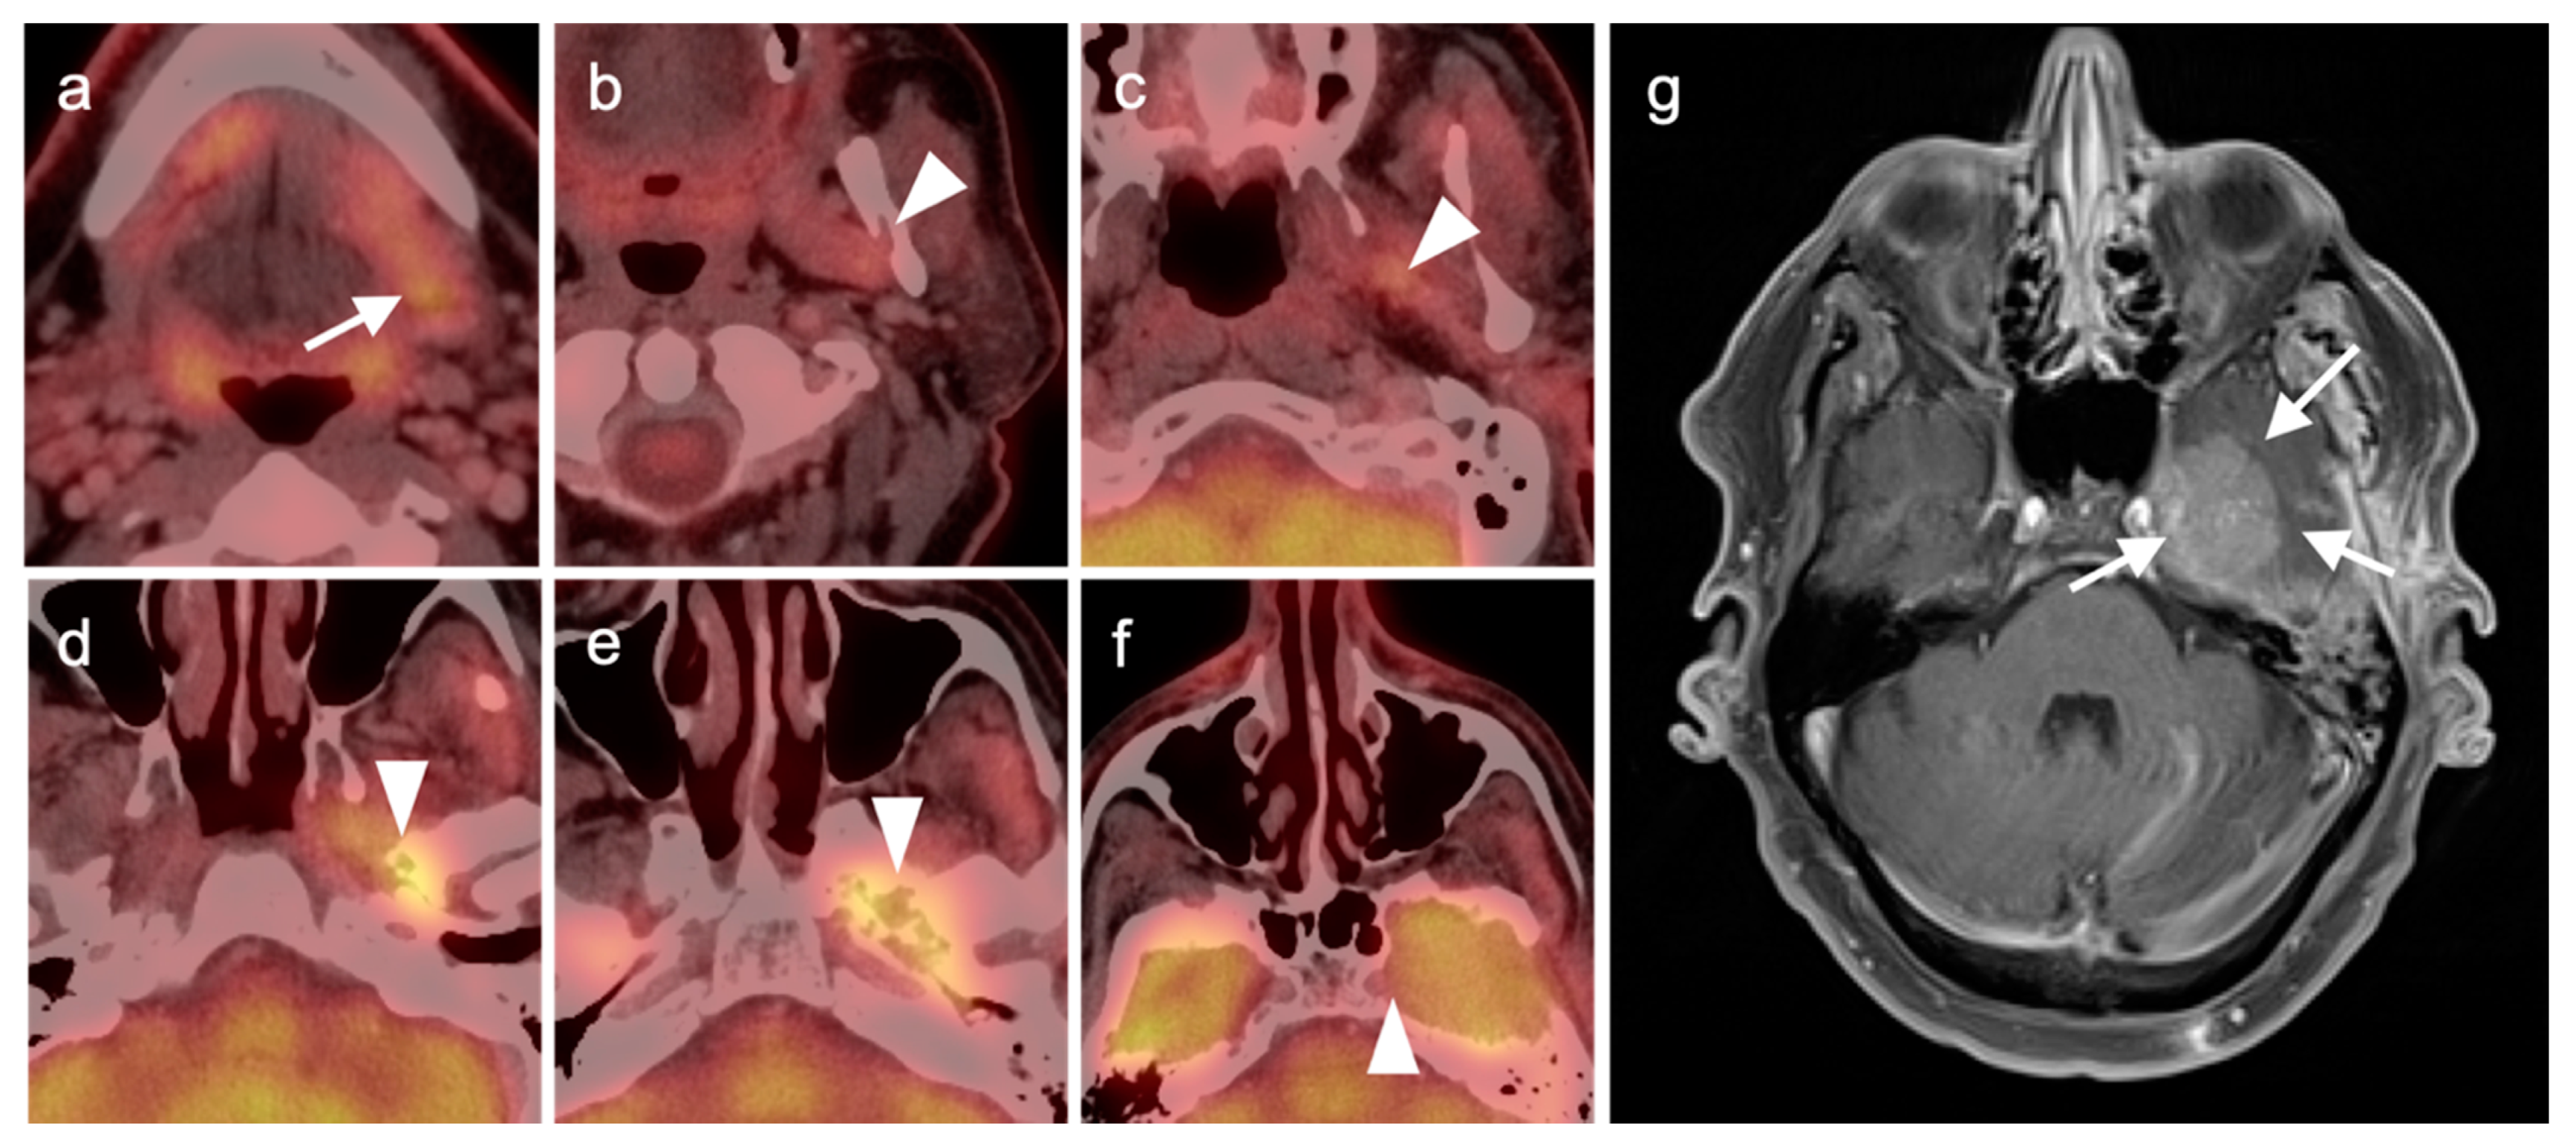

2.3. Nasopharyngeal Carcinoma